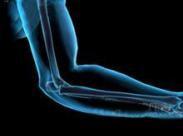

• 前臂動脈損傷

前臂動脈損傷多為利器傷所致,車禍撞擊傷也是常見原因。多見于20~40歲青壯年。前臂動脈主要有橈動脈、尺動脈和骨間總動脈以及至手部形成的掌淺弓和掌深弓。掌淺弓和掌深弓...